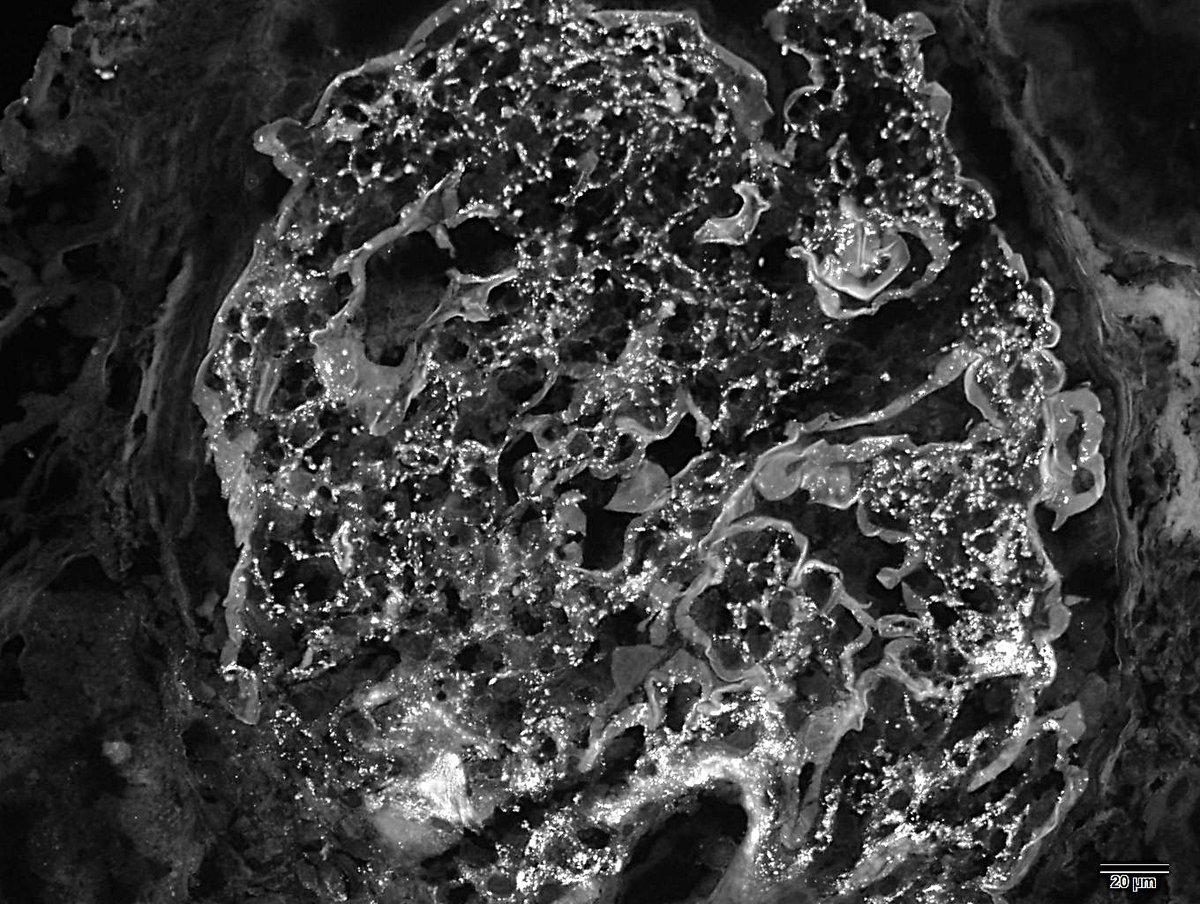

Trichilemmal carcinoma Lobules with sharp borders continuous with the epidermis Cytoplasm vacuoles Atypical cells Trichilemmal keratinization Peripheral palisading #path #pathology #medicine #dermatology #dermpath #derm

Trichilemmal carcinoma

Lobules with sharp borders continuous with the epidermis

Cytoplasm vacuoles

Atypical cells

Trichilemmal keratinization

Peripheral palisading